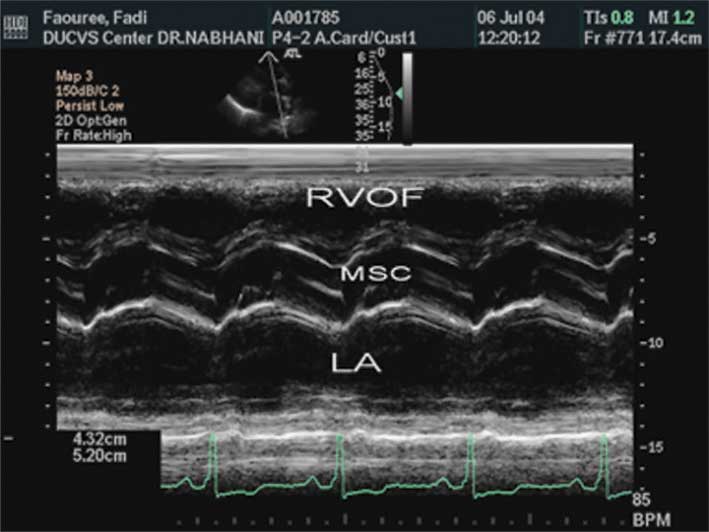

ج- حركة الصمام التاجي للأمام في أثناء الانقباض (الشكل4).

|  |  |  |

| الشكل (3) ضخامة البطين الأيسـر المركزية اللامتناظرة. | الشكل (4) حركة الصمام التاجي للأمام في أثناء الانقباض. | الشكل (5) انغلاق الصمام الأبهري في منتصف الانقباض. |